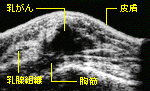

乳がん初期に威力を発揮するマンモグラフィーによる診断 ふつうよりも波長の長いX線を使用したX線の乳房の撮影を、マンモグラフィーという。乳がんの初期など、従来のX線には写らない小さながん組織の影も、小さい石灰化の像の存在で発見できる。左上は、乳がんの超音波画像。 |